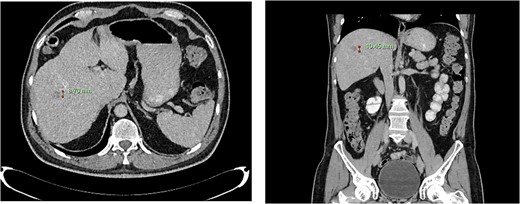

Computed tomography dated 25 September 2012 of the abdomen and pelvis measuring 18.65 mm (anterior–posterior) lesion at liver segment 5/6 in axial (left) and coronal (right) view.